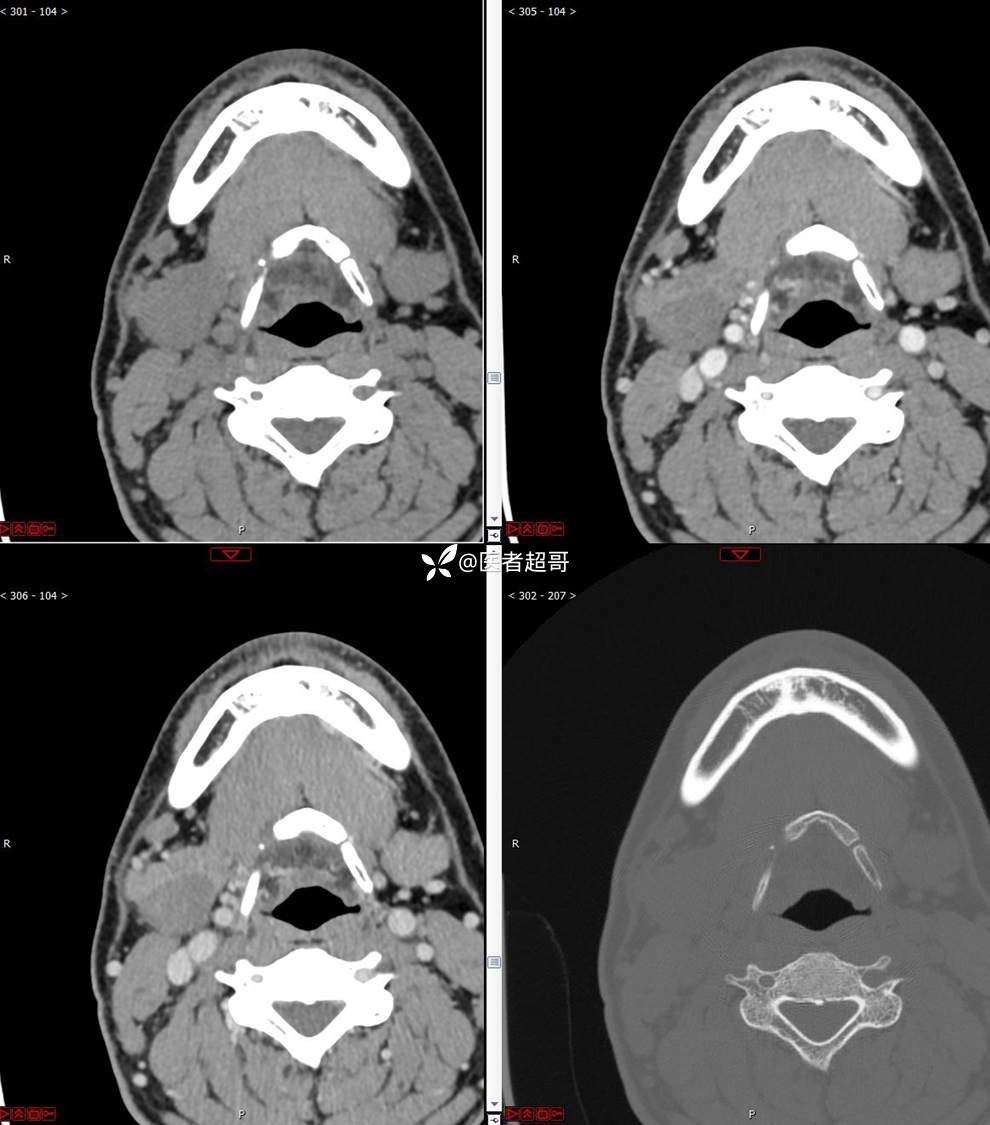

颌下腺结节:青年男性,颌下区无痛性肿物,请分析~~~

主 诉:发现右颌下区无痛性肿物1年。

现病史:患者于1年前发现右颌下区一肿物,肿物约“葡萄粒”大小,无疼痛不适,无进食时颌下区肿胀及疼痛不适。2023-10-1就诊于市中医院行超声检查;未予治疗。肿物体积无明显变化,求进一步治疗就诊于我院门诊,门诊以“颌下肿物”收入我科。患者自发病以来,神志清,精神佳,食欲好,睡眠好,大小便正常,近期体重无明显变化。